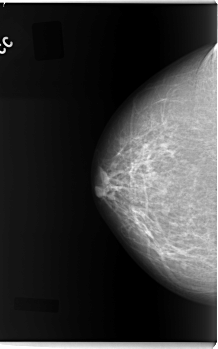

C_0088_1.LEFT_MLO

FILE: C_0088_1.LEFT_CC.OVERLAY

TOTAL_ABNORMALITIES 1

ABNORMALITY 1

LESION_TYPE MASS SHAPE OVAL MARGINS MICROLOBULATED

ASSESSMENT 5

SUBTLETY 5

PATHOLOGY MALIGNANT

TOTAL_OUTLINES 1

BOUNDARY